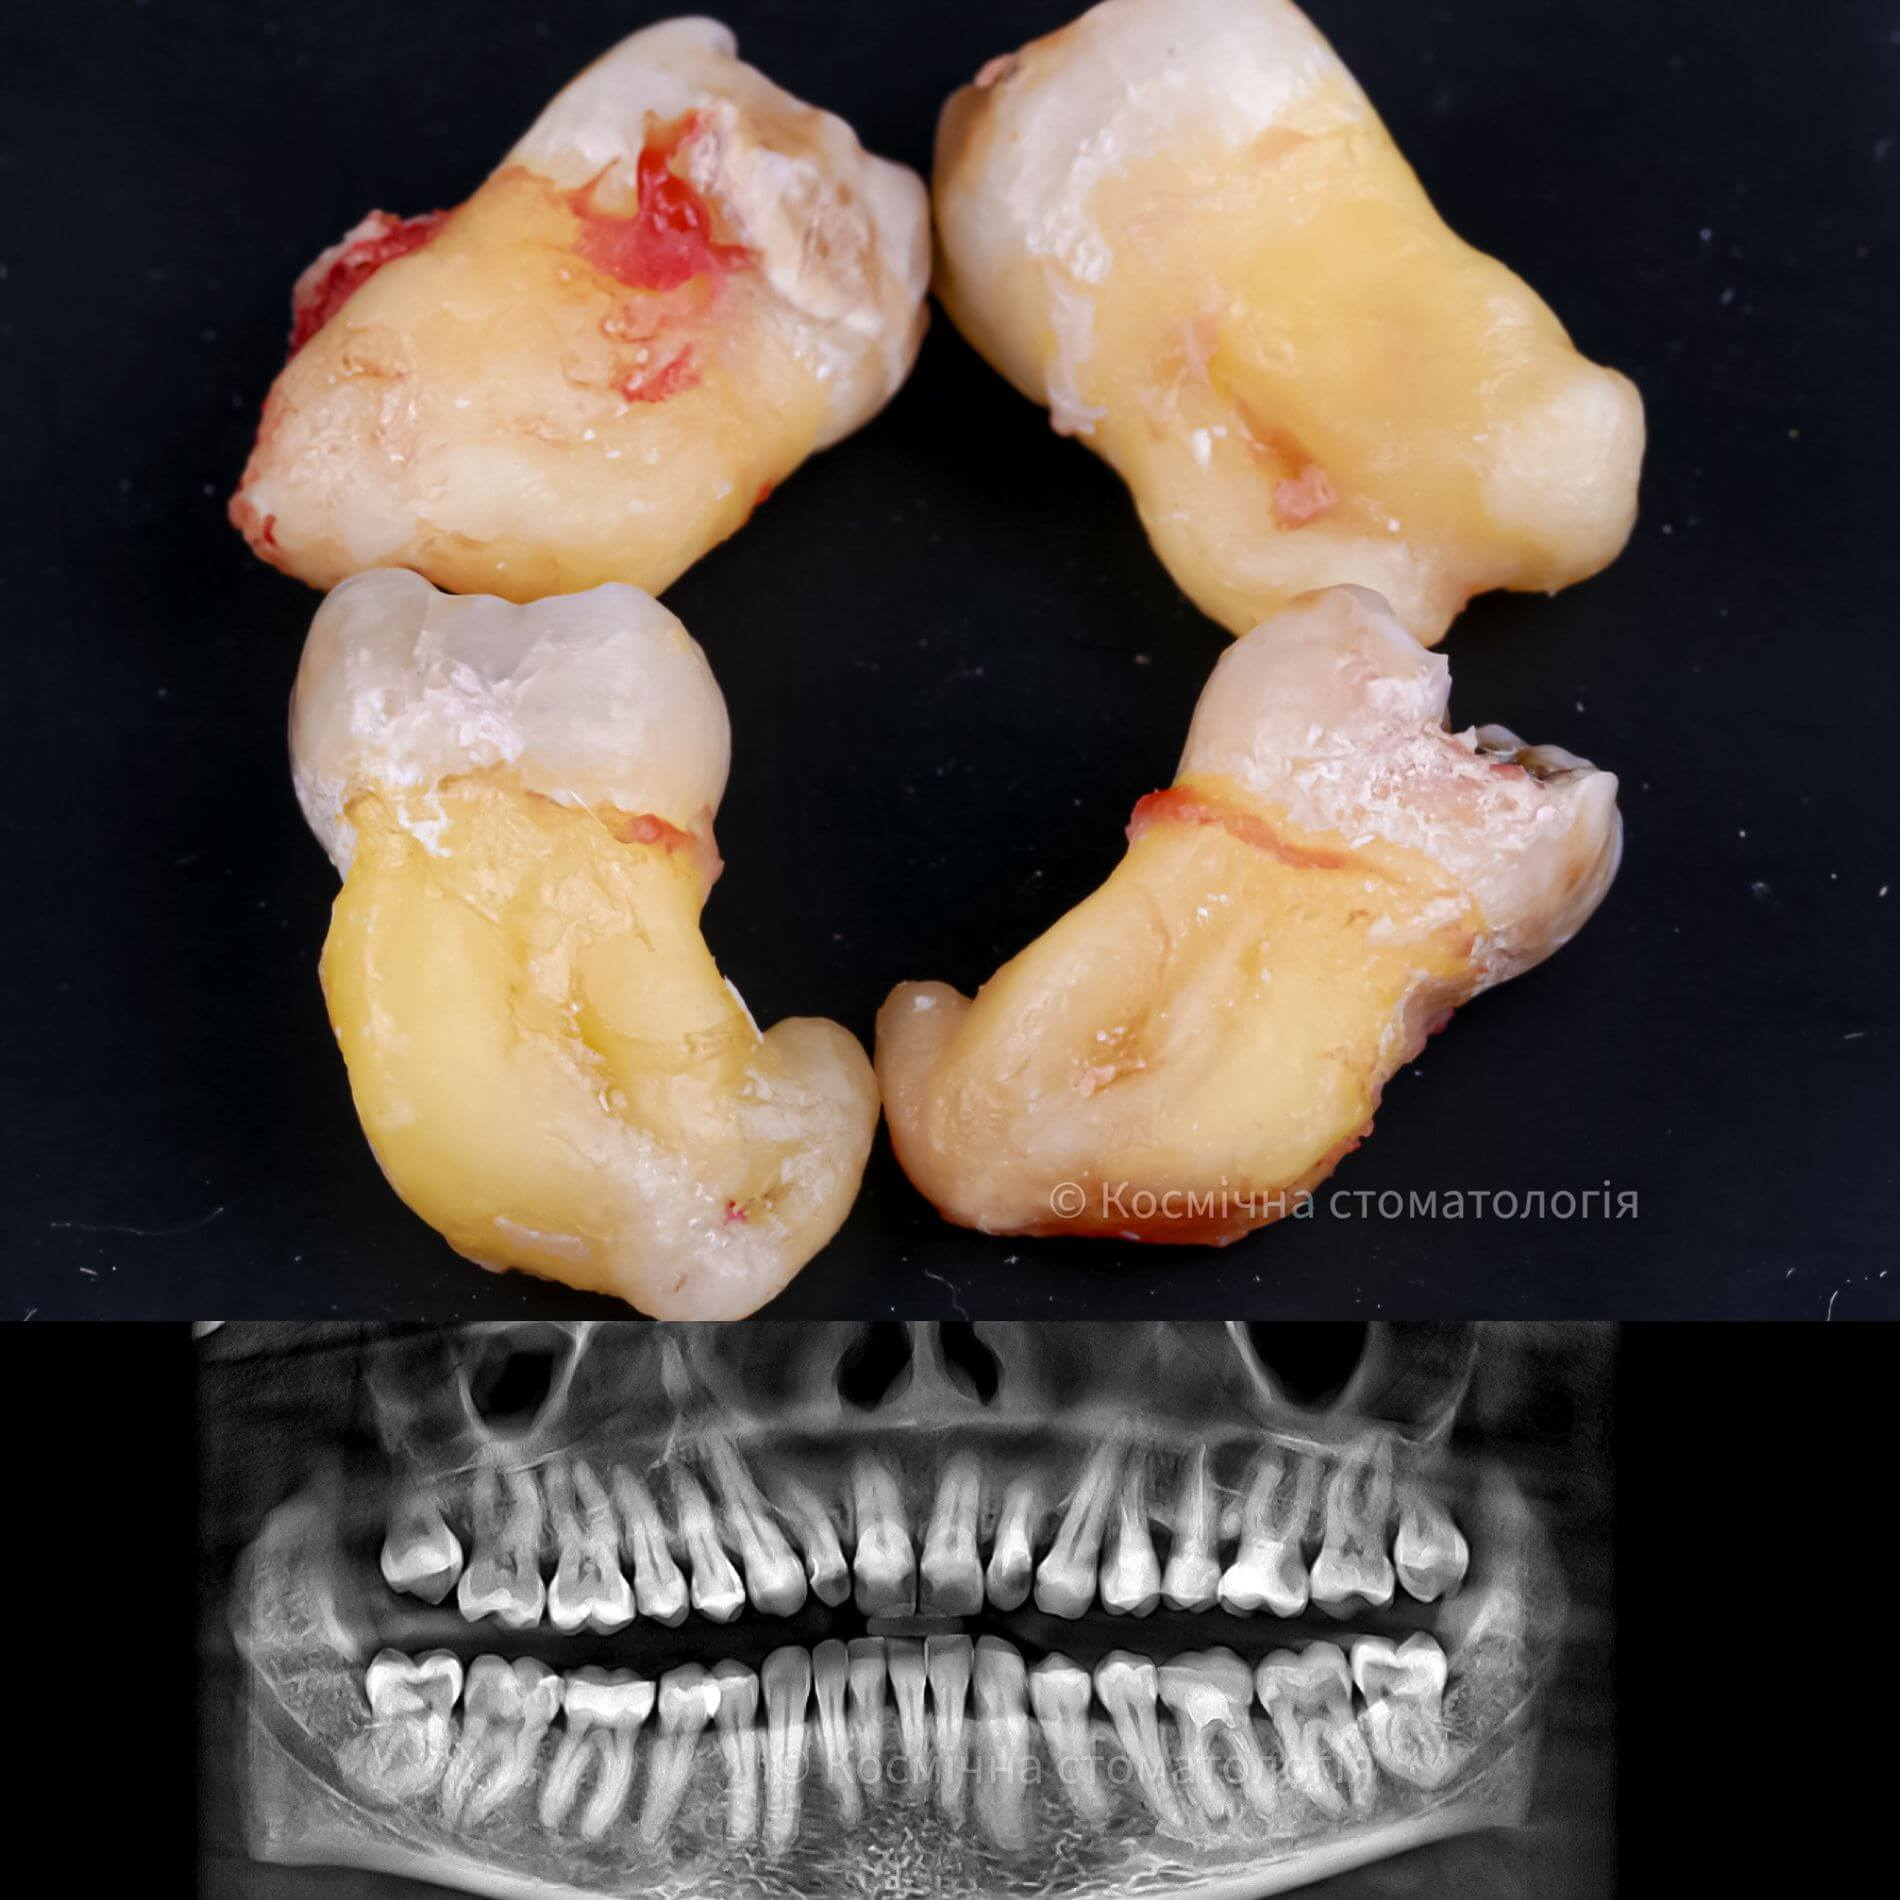

• Полное удаление зуба - если зуб полностью прорезался и имеет сросшиеся корни.

• Отдельное удаление коронки зуба и его корней - если зуб прорезан и корни растут по отдельности.

Галерея